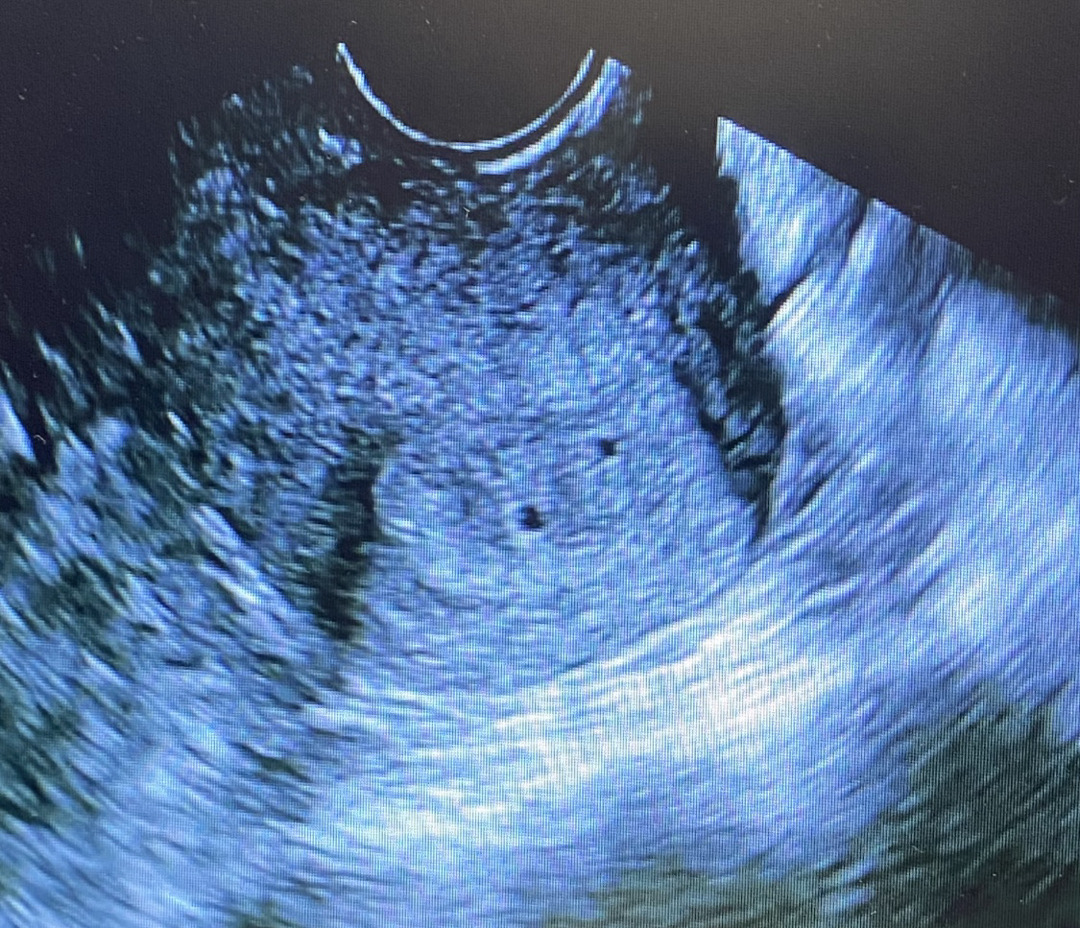

4주 5일차

시험관으로 오래 기다리던 임신 드디어 성공했네요. 안정기까지 걱정이지만 잘 먹고 잘 자고 잘 지내보려구요! 애기집 보러 갔는데 하나는 작지만 2개의 애기집이 보이더라구요. 아직은 확실하지는 않다고 확실하게 토요일에 초음파 보자시네요. 5일 기다림이 마치 5개월 같네요~ 2개의 애기집이 잘 커주길 바랄뿐이에요. 너무 작아보이나요? ㅠ ㅠ

ㅠㅠ 좀..작데요 출혈있어서 두번진료받았는데 기다려보는 수 밖에 없어서 주말 내내 눕눕했네요ㅠㅠ 너무 불안하고 시간이 안가요 흑